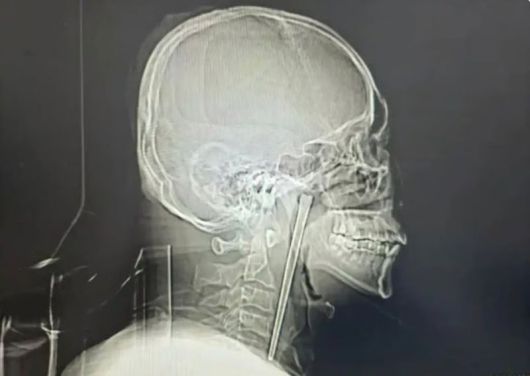

19일(현지시간) 사우스차이나모닝포스트(SCMP)에 따르면 왕씨라는 남성은 이달 초 다롄 시립 중앙병원에서 목에 박혀 있던 금속 젓가락을 제거하는 수술을 받았다.

그러나 최근 들어 아침 기상 시와 음식물을 삼킬 때 통증이 심해지자 다시 병원을 찾았고, 정밀 검사 결과 젓가락이 입천장 뒤쪽에 위치한 연구개 부위에 박혀 있는 것으로 확인됐다.

다행히 주변 점막 손상이나 성대 기능 이상은 발견되지 않았다. 왕씨가 또다시 목 절개 수술을 거부하자 의료진은 구강을 통한 최소 침습 수술을 선택했고, 비교적 적은 출혈로 젓가락 제거에 성공했다. 이후 그는 빠르게 회복해 수일 만에 퇴원했다.